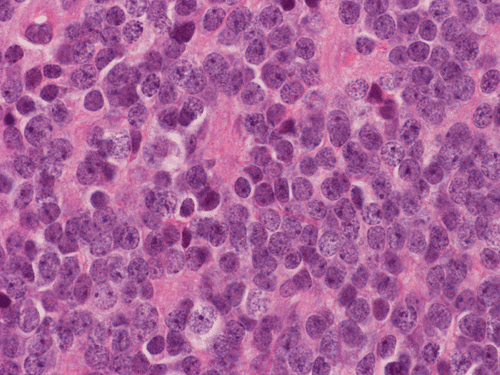

Pathology of the Case: The tumor is composed of neoplastic small blue cells on the cytologic preparation (Pancel C and D) with only minimal amount of cytoplasm. On frozen section (Panel E and F), the tumor cells are packed in solid sheets without specific pattern of arrangement. On permanent sections, the tumor again is composed of solid sheets of small blue cell tumors with rather monotonous nuclei (Panel G and H). In some areas, there is some small neuropil islands (Panel I). No distinct perivascular coronary arrangement is noted.  (Panel J). There is a moderate labeling index on Ki67 (Panel K). The tumor cells are strongly positive for neurofilament proteins (Panel L). Some large stellate, cells positive for glial fibrillary acidic protein (GFAP) are also present and these cells may represent reactive astrocytes (Panel M).

DIAGNOSIS: Pineal parenchymal tumor of intermediate differentiation, WHO grade II.

Pineoblastoma (WHO grade IV), PPTID (WHO grade II-III), papillary pineal tumor (WHO grade II-III), and pineocytoma (WHO grade I) comprise a spectrum of small blue cell tumors with variable level of differentiation and malignant potential.

In essence, PPTID is composed of diffuse sheets or large lobules of  uniform cells with mild to moderate nuclear atypia and low to moderate levels of mitotic activity.  Differentiation of grade II and III tumors can be made based upon a combination of mitotic activity levels and neurofilament protein immunoreactivity. Rare mixed tumors exhibiting characteristic elements of both pineocytoma and pineoblastoma have also been classified as PPTID, albeit somewhat controversially. The tumor classification of PPTID originated in 1993 with the work of Schild, et al. reviewing data on 30 patients with pineal parenchymal tumors diagnosed between 1939 and 1991. Of the 30 pineal parenchymal tumors, four were sub-classified as PPTID by Schild and his colleagues 9.

PPTID has a histopathologic picture of a small blue cell tumor. However, the degree of pleomorphism is not as high as pineoblastoma or medulloblastoma. Particularly for the one with better differentiation, the cells would have overall features suggestive of lymphocytes. This would further suggest germinomas as they are associated with a substantial amount of lymphocytes. Search for large germinoma cells would be the diagnostic clue to distinguish these two categories. Histological distinction of PPTID with teratomas, yolk sac tumors, embryonal cell carcinomas, and choriocarcioma components in germ cell tumors is relatively straightly forward. The table below provides comparison of different types of pineal parenchymal tumors.